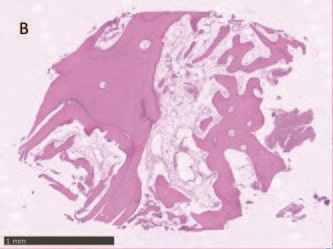

Гістологічний аналіз показав добре організовану, в основному зрілу тканину, утворену компактною пластинчастою кісткою, що характеризується чітко окресленими кістковими пластинками навколо каналів Гаверсіяна та Фолькмана, оточених меншими ділянками, в яких пластинки були менш організованими та багатими остеоцитами на стадії дозрівання . Кількість знайденої мінеральної матриці - від 69% до 72% - була особливо значною.

Запального інфільтрату не спостерігалося.

Рис. 9 – Фрагмент В зразка кістки, взятий у 4,5, показує широкі ділянки зрілої кісткової тканини та медулярного компонента.